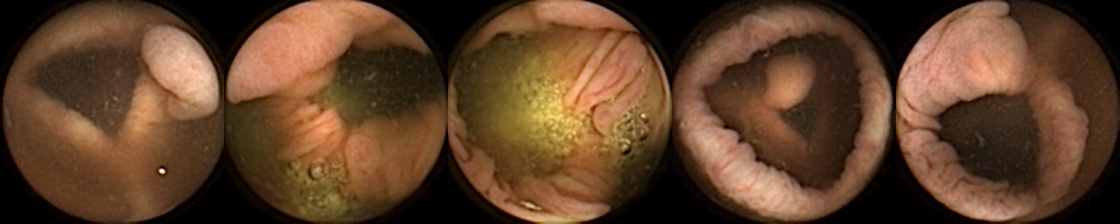

Similarly, we consider examples for the MIV model based on SimCLR pretraining using the pretrained ConvNext backbone in Figure 4. The model has a test accuracy of 86.26% for DBA L1 with 2 heads. Here we note again a similar trend by looking at the True Positive and False Negative examples as observed before, where a significant difference in the query image when compared with the target images can lead to a failure to identify the same polyp images in the five examples. A look at the False Positive examples affirms that the task remains challenging, as evidenced by the model’s occasional misclassifications in ambiguous cases.

True Positive False Negative

False Positive True Negative

Figure 4: True Positives (Pred = true, Label = true), False Negatives (Pred = false, Label = true), False Positives (Pred = true, Label = false),True Negatives (Pred = false, Label = false) for the DBA L1(h=2) model applying SimCLR using the ConvNeXt backbone. In each row, the leftmost image is the query and the 4 images to the right of each query are the target images.